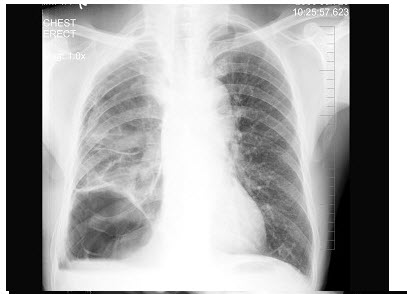

32、单项选择题

男,66岁,咳嗽、发热2周余,无痰中带血,X线检查如图,最可能的诊断是()

A.细支气管肺泡癌

B.血行播散型肺结核

C.左肺浸润型肺结核

D.左肺炎症

E.肺转移瘤

点击查看答案